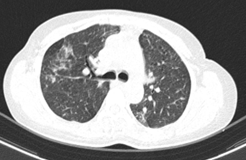

Hình 9: Hình ảnh sau 6 tháng điều trị: Các đám đông đặc và kính mờ 2 phổi (giảm số lượng và kích thước sau các đợt điều trị).